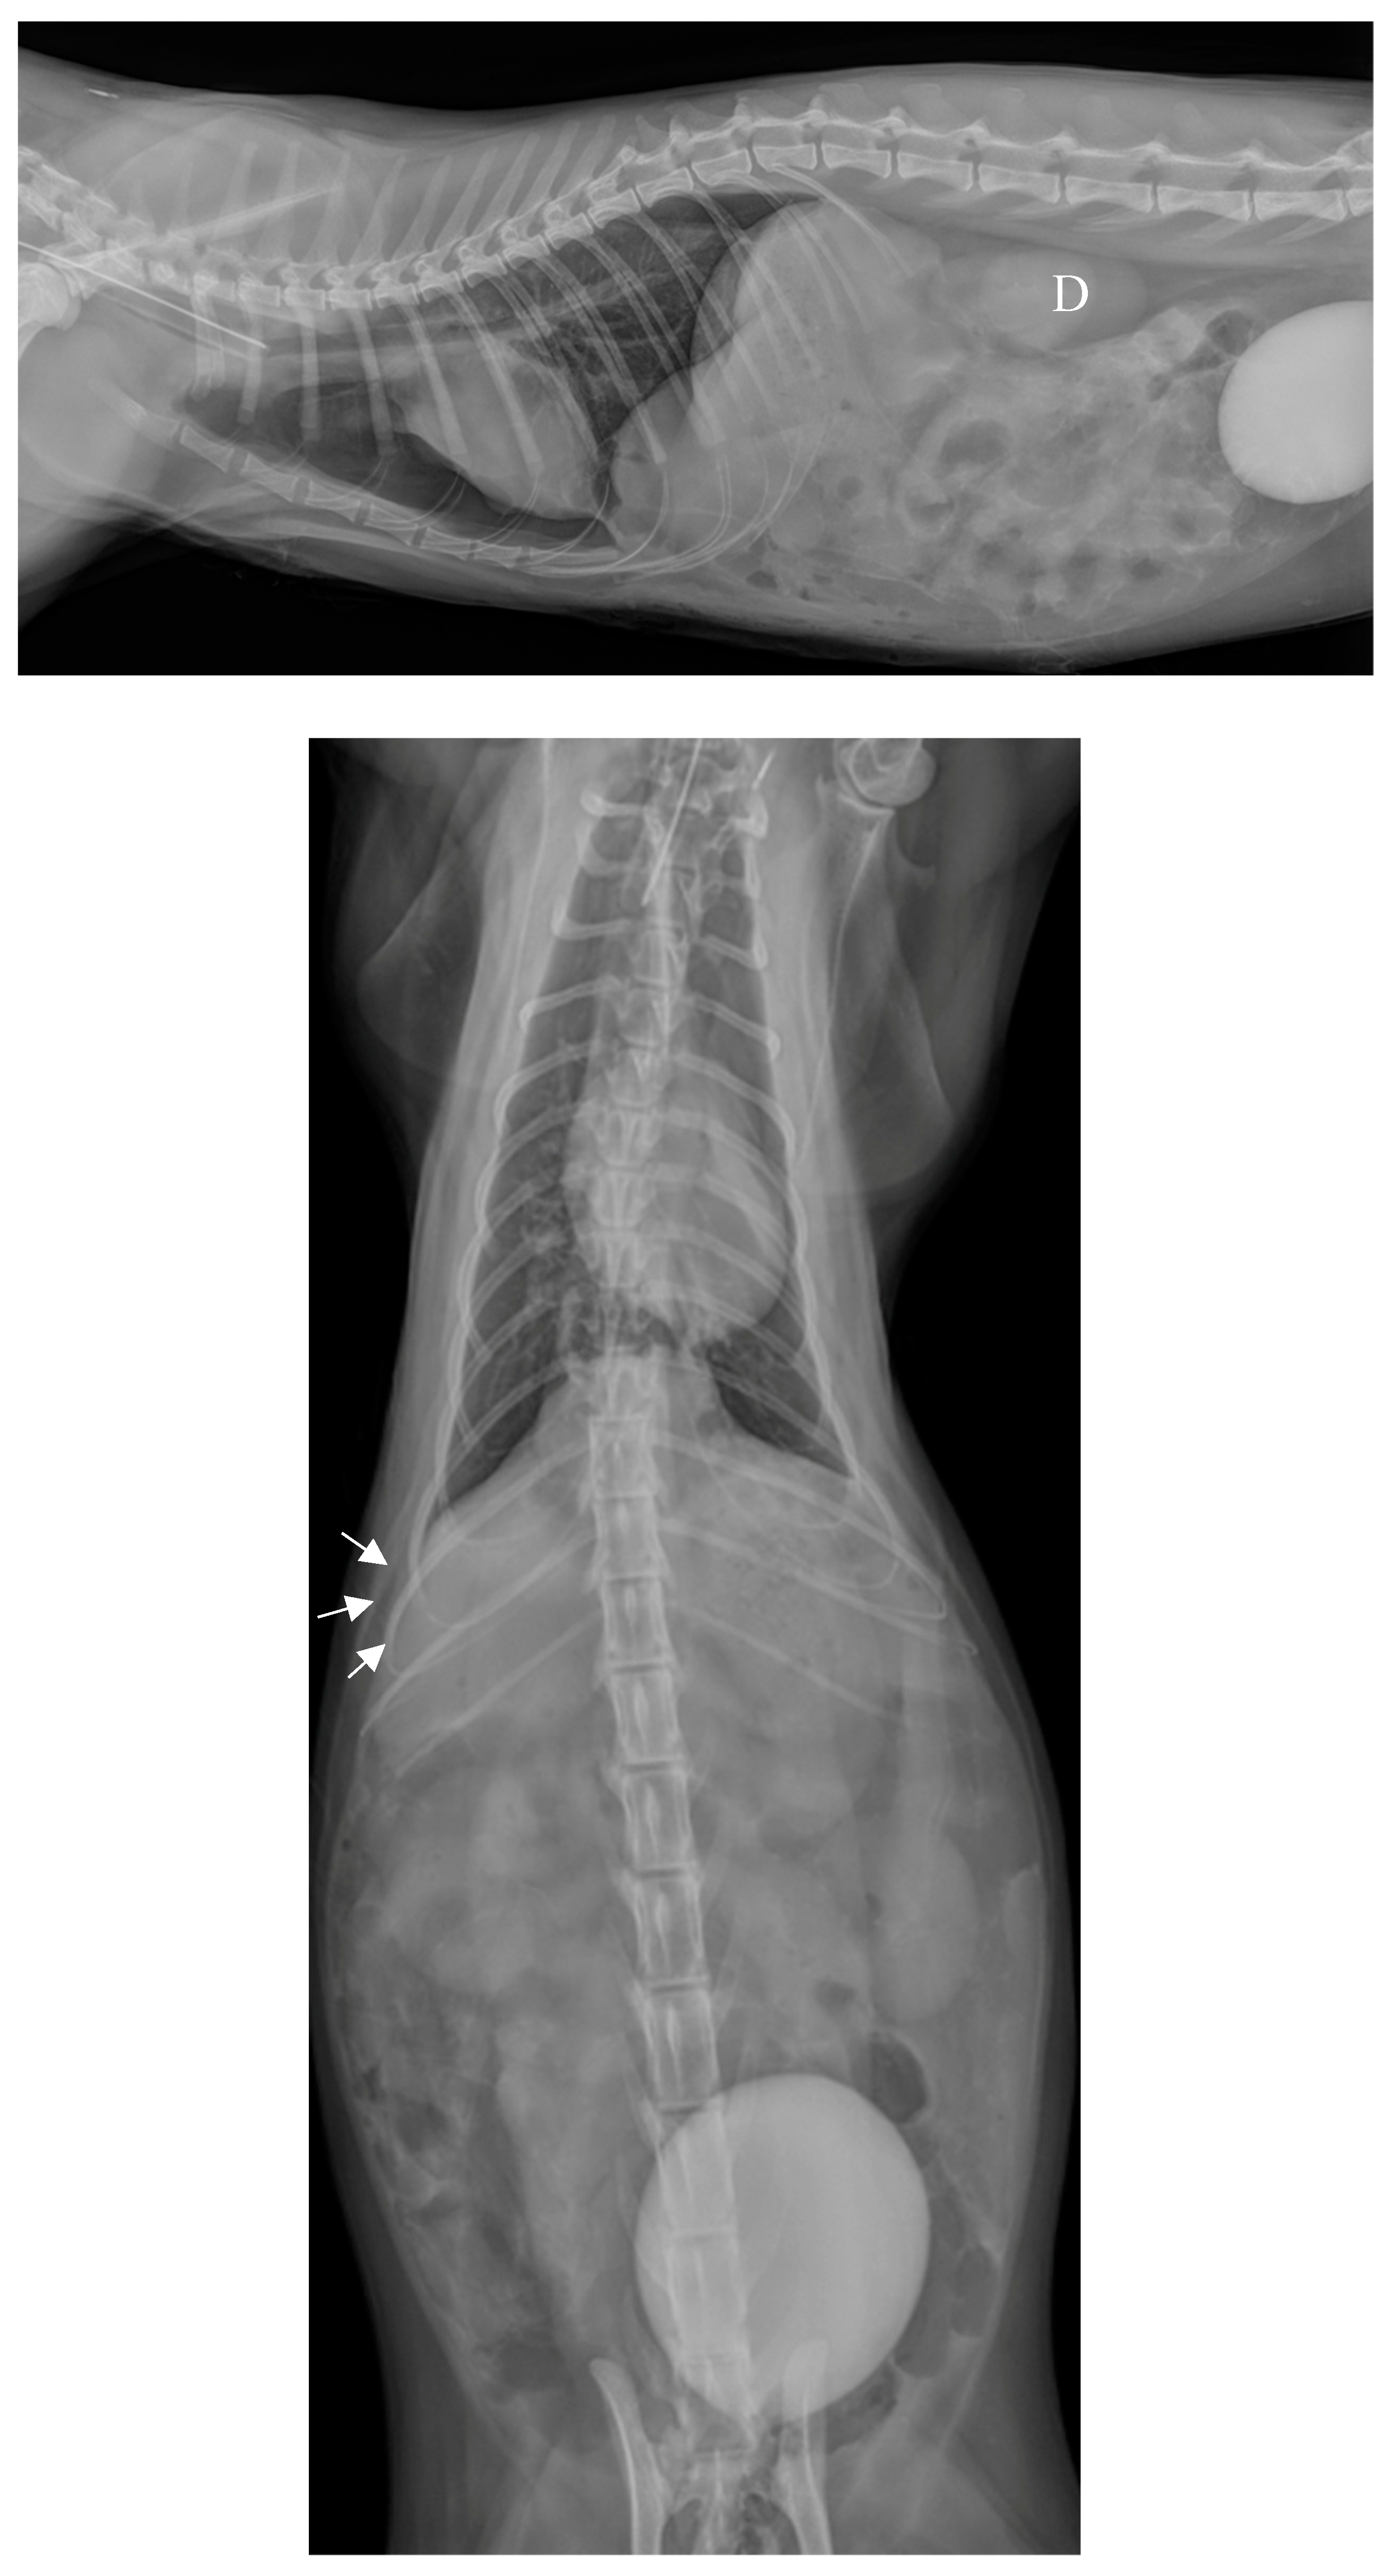

Plain chest radiographs identified a large mass (4 cm x 4 cm), well circumscribed, homogeneous, with a density similar to soft tissue, located in the usual projection area of the thorax, caudally and ventrally on the lateral projection, medially and just right to the spine on the dorsoventral projection, in contact with the sternum, the diaphragm and the apex of the heart, ventrally to the caudal vena cava (Figure 1a,b). The rest of the thoracic cavity appeared unremarkable.

This finding, in the context of a fall from the second floor, raised the possibility of the liver or other abdominal organs being implicated in a traumatic diaphragmatic rupture; however, the mass was notably circumscribed. The differential diagnosis included an incidentally discovered mass (granuloma, hematoma, abscess, cyst, neoplasia), a longstanding traumatic diaphragmatic hernia, or a congenital diaphragmatic hernia.

Among congenital diaphragmatic hernias, the very ventral location excluded a hiatal hernia; on both lateral and frontal radiographs, the mass did not appear to be in continuity with the pericardial sac: the contours of the heart were clearly observable and the edges of the pericardial sac were clearly separated from this mass, which did not support the diagnosis of a peritoneopericardial hernia; a pleuroperitoneal hernia was deemed the most likely diagnosis.

Figure 1. Chest radiographs on admission. a. Profile view (latero-lateral) in right decubitus position. b. Front view (dorso-ventral).